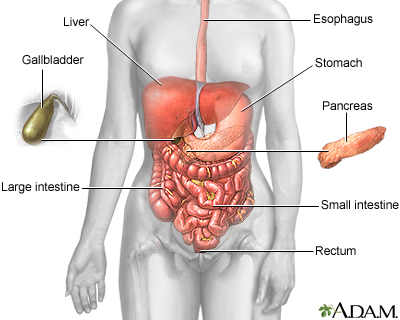

The pancreas is an organ located behind the stomach. It produces the hormones insulin and glucagon. It also produces chemicals called enzymes needed to digest food.

Most of the time, the enzymes are active only after they reach the small intestine.

- If these enzymes become active inside the pancreas, they can digest the tissue of the pancreas. This causes swelling, bleeding, and damage to the organ and its blood vessels.

- This problem is called acute pancreatitis.

- Gallstones are the next most common cause. When the gallstones travel out of the gallbladder into the bile ducts, they may block the opening that drains bile and enzymes. The bile and enzymes "back up" into the pancreas and cause swelling.